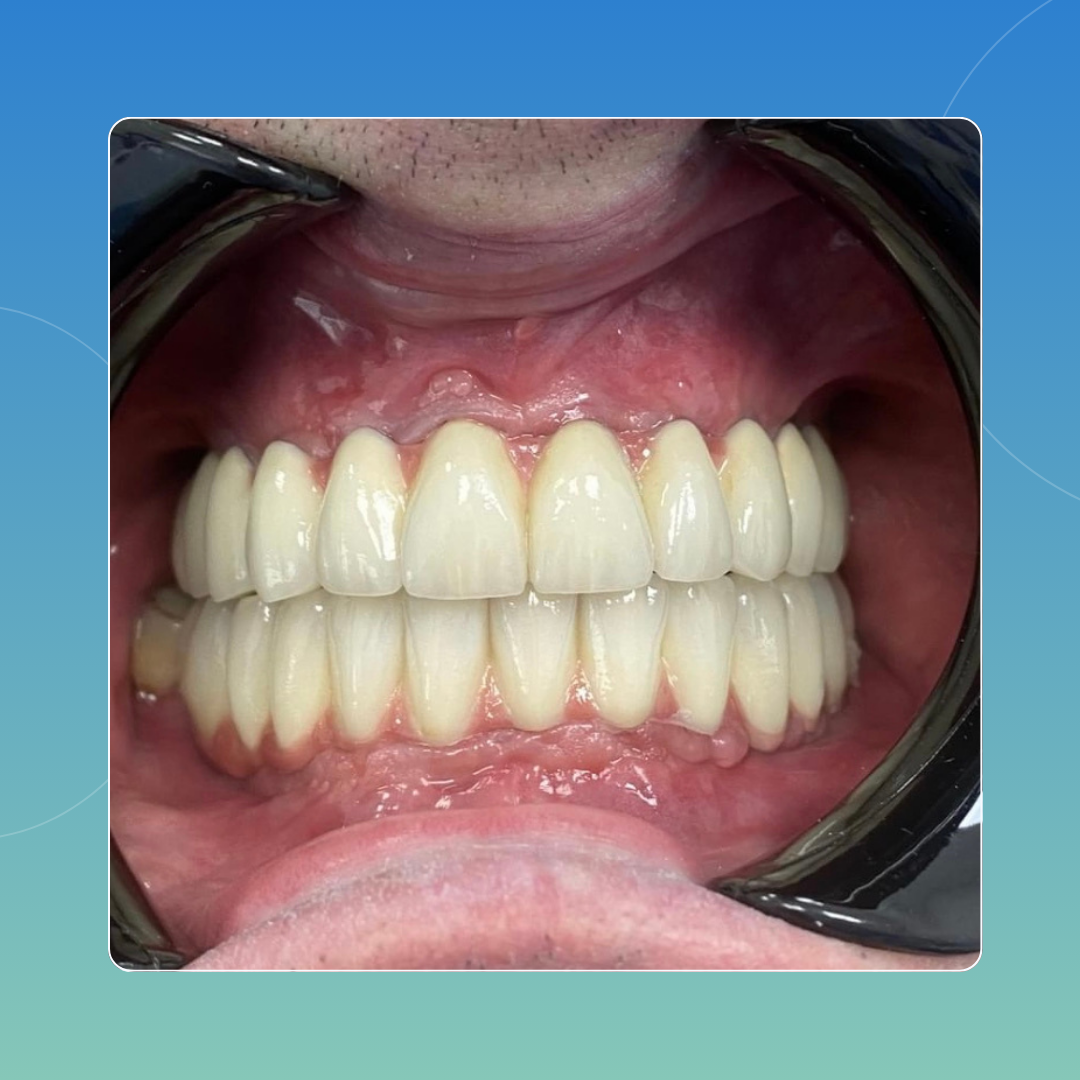

CASI CLINICI

Approccio personalizzato, esiti documentati

Di seguito riportiamo casi analizzati e svolti all’interno del nostro poliambulatorio che pensiamo possano rendere a pieno ciò che è per noi il nostro lavoro: passione e attenzione ai dettagli, volendo sempre il risultato migliore possibile che possa dar contentezza al paziente e a noi stessi